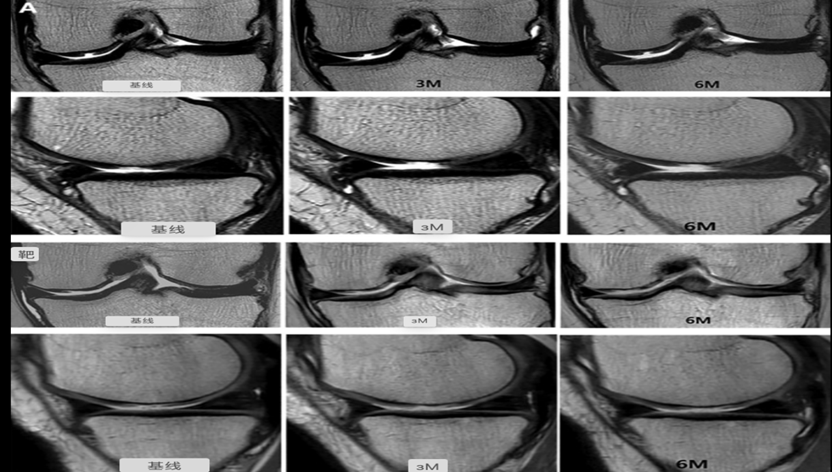

JOINTSTEM的实验,在12名患者中关节内注射了MSC,结果与其他12名接受生理盐水溶液的患者(对照组)进行比较。据作者称,注射MSC可以促进患者骨骼功能的恢复,而且减轻了疼痛,没有副作用[2]。

注射MSC可以促进软骨生长恢复 图源文献2